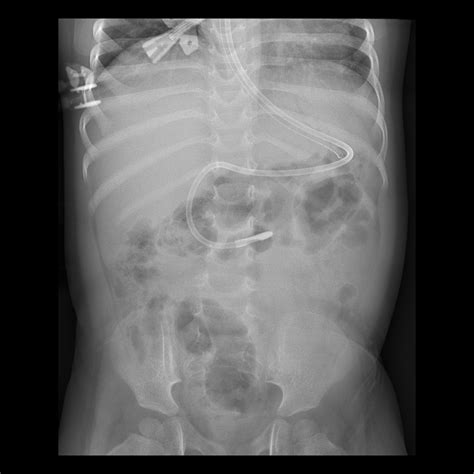

Radiography (X-Ray) The gold standard. An abdominal or chest X-ray provides definitive visualization of the tube tip in the stomach.

• nd tube placement x ray